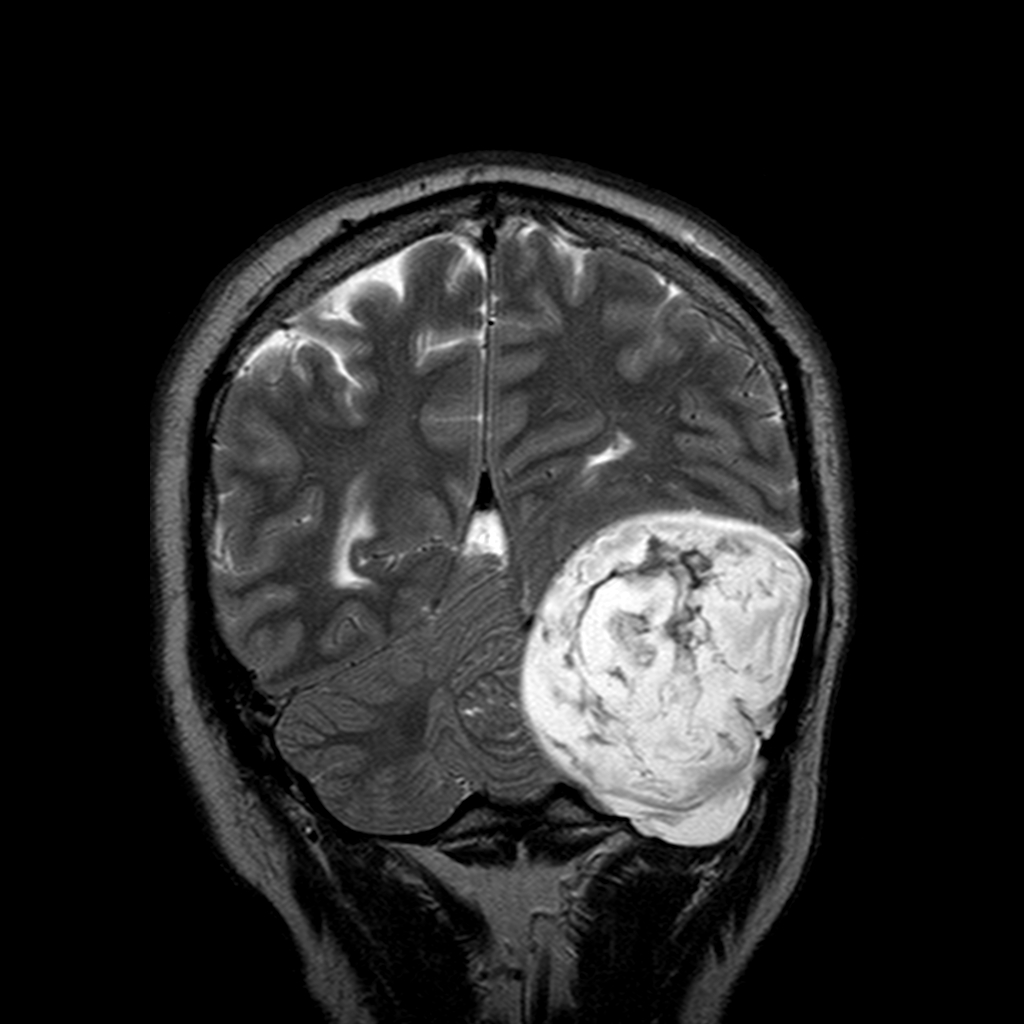

МРТ головного мозга: показания и результаты

Раздел: Визуальный дайджест